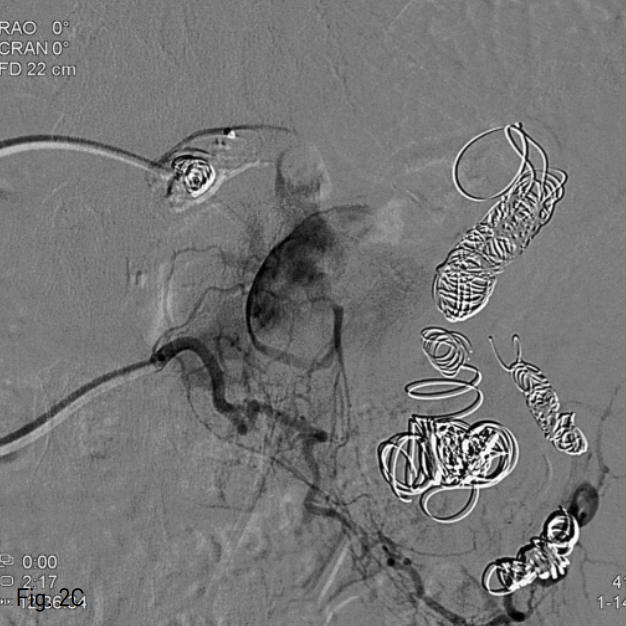

우측 총대퇴동맥을 천자한 후, 5 Fr sheath (Terumo, Tokyo, Japan)를 거치 시켰다. 이후 0.035 inch guide wire (Terumo, Tokyo, Japan)와 5 Fr Roche-Hepatic ca theter (Cook, Bloomington, IN, USA)를 이용하여 비장동맥 조영술을 시행하였으며, 근위부 1/3 지점에 약 4cm 크기의 가장 큰 비장동맥류가 관찰되었다 (Fig. 2A). 2.2 Fr microcatheter (Progreat; Terumo, Tokyo, Japan)을 이용하여 가장 원위부에 있는 동맥류를 지나 비장 문까지 진입한 후 11개의 nester coil (Cook, Bloomington, IN, USA)을 이용하여 색전을 시행하였다. 그 후 microcatheter를 근위부로 옮겨 가장 큰 비장동맥류의 원위부와 근위부에 13개의 nester coils, 1개의 vascular plug, 그리고 histoacryl 1:3 mixture를 이용하여 색전하였다. 색전술 후 복강 동맥 조영술 상 비장동맥은 완전히 색전되어 조영되지 않았으나, 가장 큰 크기의 비장동맥류에 지연기상 조영이 나타났다 (Fig. 2B). 이에 다시 2.2 F microcatheter를 우측 위그물막동맥으로 진입시켜 조영하였고, 많은 측부 곁가지에 의해 비장동맥류가 조영되었다 (Fig. 2C). 다시 histoacryl 1:5 mixture를 이용하여 색전하였으며, 복강동맥 조영술상 더 이상 비장동맥류는 관찰되지 않았다.

Fig. 2

C. Right gastroepiploic angiogram shows multiple fine feeders to largest splenic artery aneurysm.